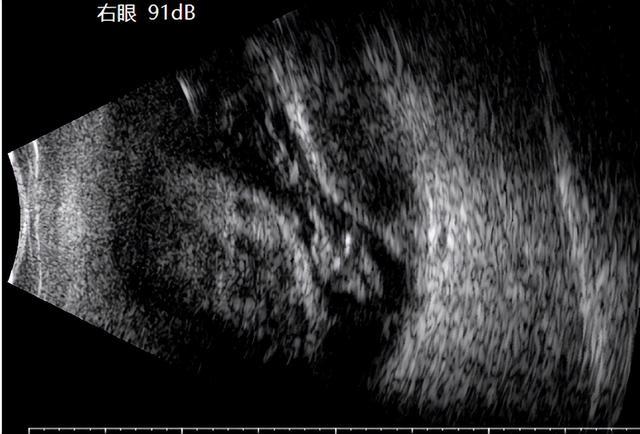

两例患者最终均实现视网膜解剖复位,两位患者术后前房恢复透明,人工晶体位置稳定,患者1的矫正视力恢复到0.15,尽管SCH的总体预后仍不乐观,但及时规范的治疗可最大限度保留,眼球结构和残存视力。

(▲患者1术后眼底图及B超)